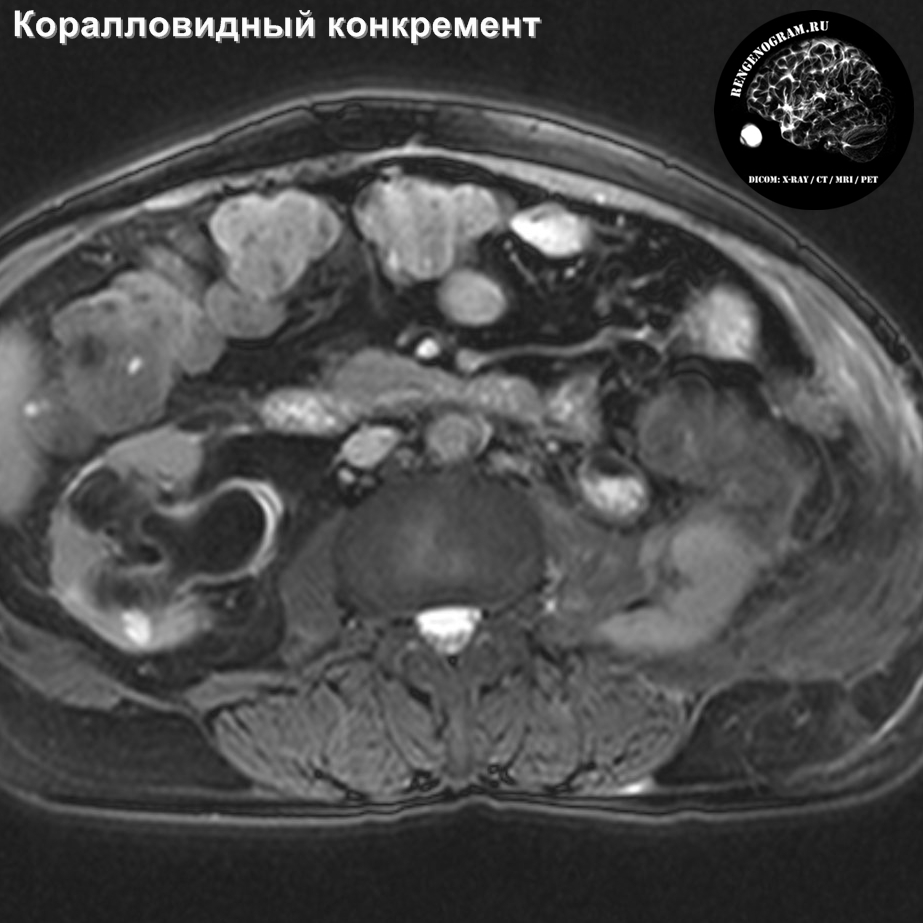

Изображения КТ конкрементов мочевого пузыря